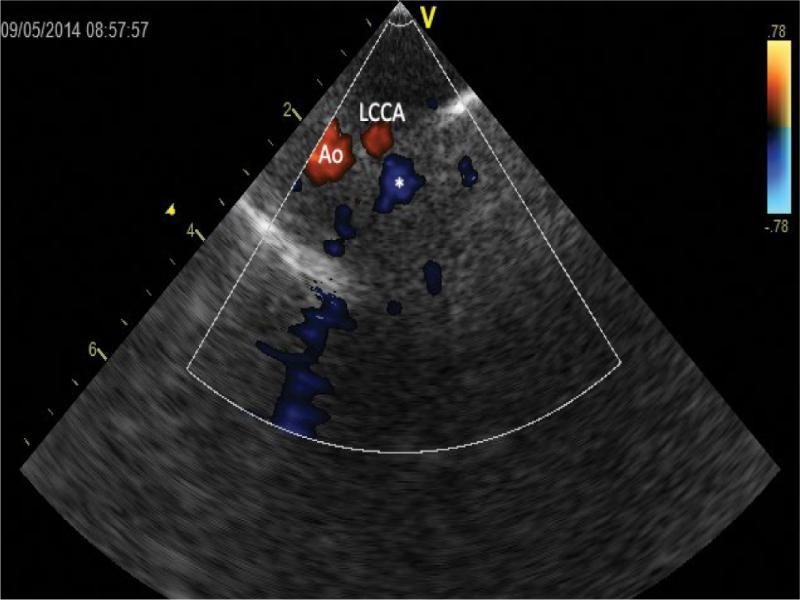

A further shift of ultrasonic beam upwards, systole. Cross-sections of the ascending aorta (Ao) and the left common carotid artery (LCCA), which runs separately at the same level – both vessels are coded in red – as well as the ductus arteriosus (*) and the pulmonary trunk (PA) – these vessels are filled with blue color, indicative of a flow in the opposite direction

Even a higher position of the plane of the beam, systole. Cross-sections of the apical portion of the aortic arch (Ao) and the left common carotid artery (LCCA) filled with red color and the ductus arteriosus (*) filled with blue color. A very close proximity of these vessels is noticeable